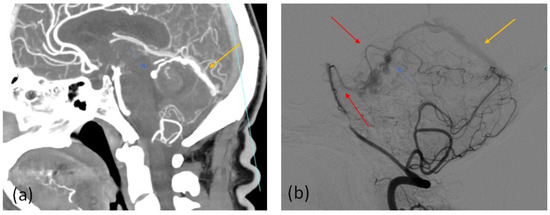

| Brain Angio CT Positive Findings | No. of Patients |

|---|---|

| Asymmetric and/or dilated feeding arteries | 7 |

| Numerous and engorged cortical veins | 15 |

| Sinus findings: | |

| 8 |

| 10 |

| 4 |

| Transcalvarial channels | 4 |